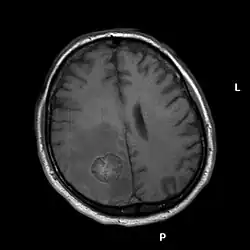

Nowotwory przerzutowe ośrodkowego układu nerwowego

Nowotwory przerzutowe ośrodkowego układu nerwowego – najliczniejsza grupa nowotworów tej lokalizacji. U dorosłych chorych najczęściej przerzutującymi do mózgowia i rdzenia nowotworami są, kolejno, rak płuc, rak sutka, rak jelita grubego i układu moczowego, czerniak, rak gruczołu krokowego, rak trzustki, rak trzonu macicy, białaczki i chłoniaki. U dzieci częstsze są przerzuty mięsaków i nowotworów germinalnych. Zdarzają się także przerzuty nowotworów złośliwych (najczęściej raka sutka i płuca) do już obecnego guza OUN (np. oponiaka)[1].

Rozpoznanie opiera się na badaniach neuroobrazowych: TK i MRI. MRI jest badaniem z wyboru w przypadku podejrzenia patologii tylnego dołu czaszki. Kolejnym etapem w diagnostyce choroby jest znalezienie ogniska pierwotnego.